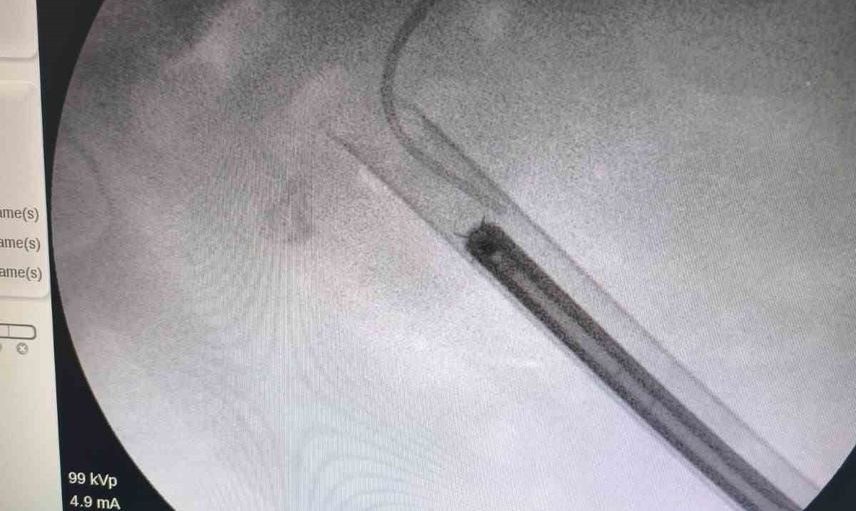

Üroloji uzmanı Dr. Miraç Ataman tarafından gerçekleştirilen müdahalede, taşın temizlenmesi için Perkütan Nefrolitotomi (PCNL) yöntemi tercih edildi. Bu yöntemde ciltten küçük bir giriş yapılarak endoskopik cihazlarla taş parçalanıp çıkarıldı. PCNL, özellikle çapı 2 cm'den büyük ve kompleks yapılı taşlarda altın standart olarak kabul ediliyor.

Vaka özelinde modern cerrahi altyapı sayesinde ciltten tek giriş yoluyla operasyon gerçekleştirildi ve böbreğin taş yükü yaklaşık 1,5 saatlik bir seansta başarıyla temizlendi. Dr. Ataman, operasyonun hem tıbbi hem de toplumsal sağlık açısından önemli bir başarı olduğunu vurguladı.